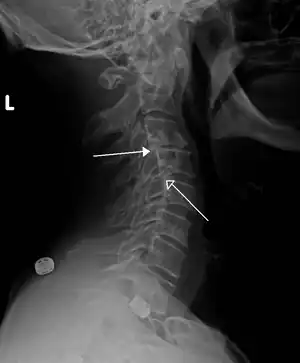

X-ray picture of a grade 1 isthmic anterolisthesis at L4-5 -